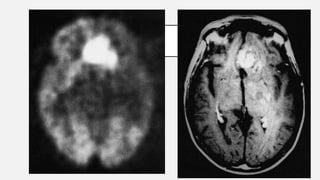

La presencia de un tumor cerebral puede ser revelada con eficacia a través

de la TAC y la REM.

El uso de un medio de contraste (yodo en el caso de TC, en el caso de RM

gadolinio), permite obtener información sobre la vascularización y sobre la

integridad de la barrera hematoencefalica, una mejor definición del nódulo

tumoral respecto al edema circundante y permite avanzar hipótesis sobre

el grado de malignidad.

DIAGNOSTICO La presencia deun tumor cerebral puede ser revelada con eficacia a través de la TAC y la REM. El uso de un medio de contraste (yodo en el caso de TC, en el caso de RM gadolinio), permite obtener información sobre la vascularización y sobre la integridad de la barrera hematoencefalica, una mejor definición del nódulo tumoral respecto al edema circundante y permite avanzar hipótesis sobre el grado de malignidad. Ballesteros M, Vargas-Carvajal. Secondary effects of the radiotherapy in the treatment of brain neoplasms. 2017. 35 (7); 313-366